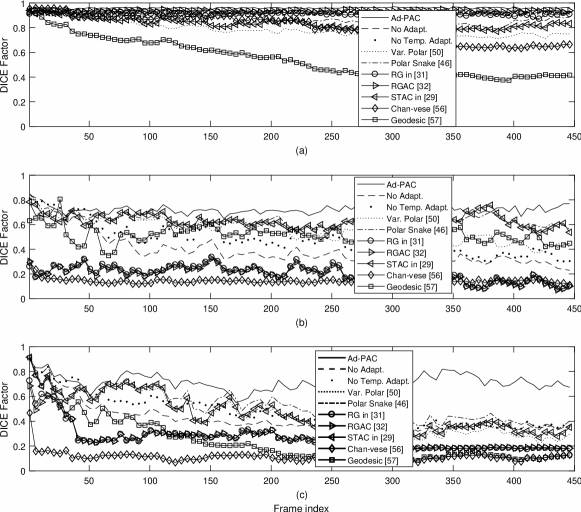

V-E Influence of Image Quality

For this study, all videos were categorized, as good, average, and poor quality videos based on the blinded expert opinion. Fig. 16 illustrates the DICE results. In good quality ultrasound videos, as per Fig. 16-(a), the proposed Ad-PAC algorithm performs very close to the manual segmentation with a DICE factor consistently above 0.95. The minimum value of DICE factors for the other algorithms range from 0.91 down to 0.37 for the Geodesic algorithm [57].

In average quality videos, as shown in Fig. 16-(b), the performance of Ad-PAC algorithm drops as low as 0.65, however, it still outperforms the other AC algorithms. Poor quality videos (Fig. 16-(c)) demonstrate the minimum DICE factor as being 0.55, still above other algorithms.

V-F Influence of IJV Shape

The IJV shape also impacts the segmentation results. Oval objects tend to be more suitable for polar representation whereas collapsed vessels tend to be much more challenging. The IJV represents a deformable model influenced by a number of factors including local anatomy, blood volume and blood flow. For this study, IJV videos are categorized into three categories being oval, 1+ apices, and fully collapsed. Fig. 16 presents the average DICE factor for the videos from each category. In Fig. 16-(a), it is evident that Ad-PAC performs close to manual segmentation when the IJV has an oval shape with a DICE coefficient greater than 0.90. The second best performance belongs to the proposed energy function without temporal adaptation having an average DICE coefficient larger than 0.83. Fig. 16-(b) shows that the IJV with 1+ apices result in the Ad-PAC performance as low as 0.50 but above other algorithms. Again, the proposed energy function without temporal adaptation is the second best algorithm with a minimum DICE factor as low as 0.48. Is is only when the IJV is fully collapsed does the Ad-PAC algorithm under-perform the algorithm without adaptation and in the worst case, the DICE factor drops to 0.19. This is a limitation of the polar contour model for fully collapsed objects such as the empty IJV.